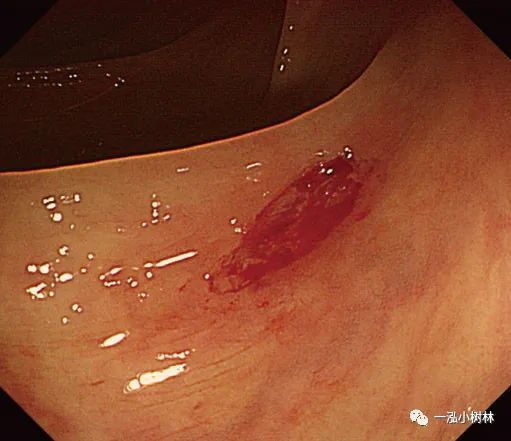

图1e 注射生理盐水下息肉切除术治疗复发性肿瘤

图1f 注射生理盐水下息肉切除术治疗复发性肿瘤